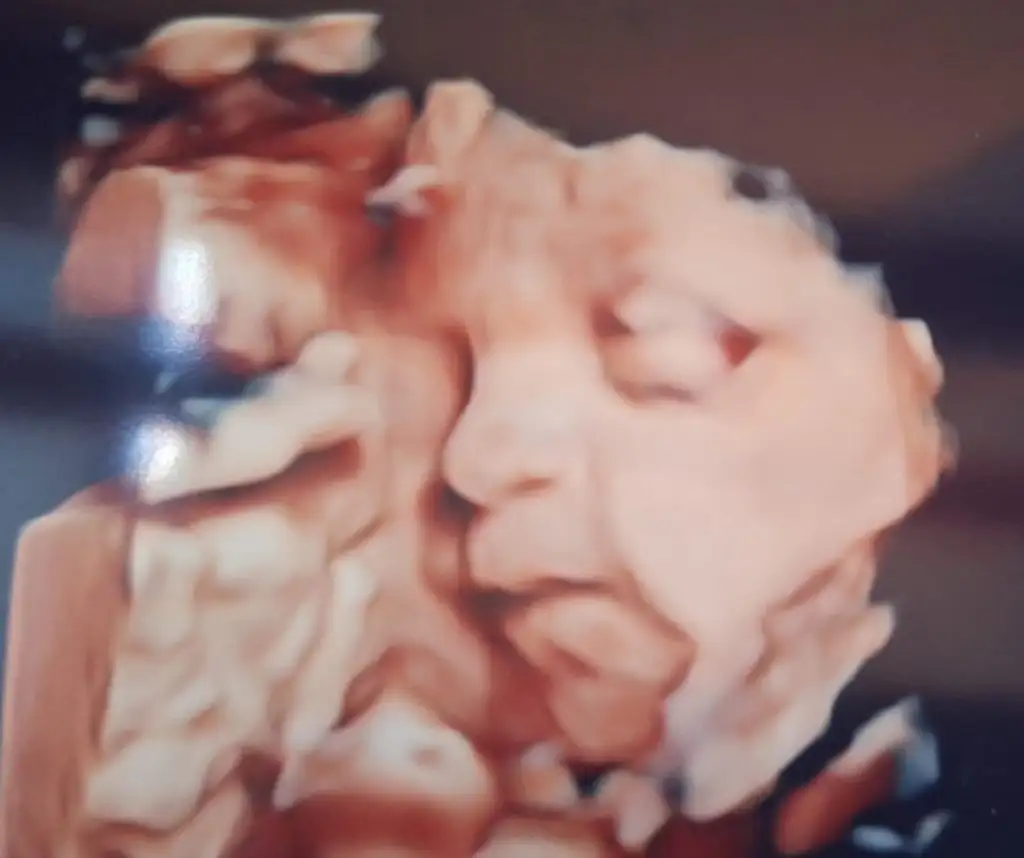

Maşallah burnuşu ağzı yanakları hep belli. Sağlıkla doğsun

Ooo maşallah , sağlıkla gelsin inşallah

Maşallah sanki biraz tosbik olcaklar gibiMaşallah burnuşu ağzı yanakları hep belli. Sağlıkla doğsunKilosu için doktor önde vs dedi mi? Benimki de dün 28+2 idim, 1358 gram çıktı. Sizinki ile benzer.

Ooo maşallah , sağlıkla gelsin inşallahne güzel baya vesikalık resim gibi olmuş

Maşallah maşallah miniğe